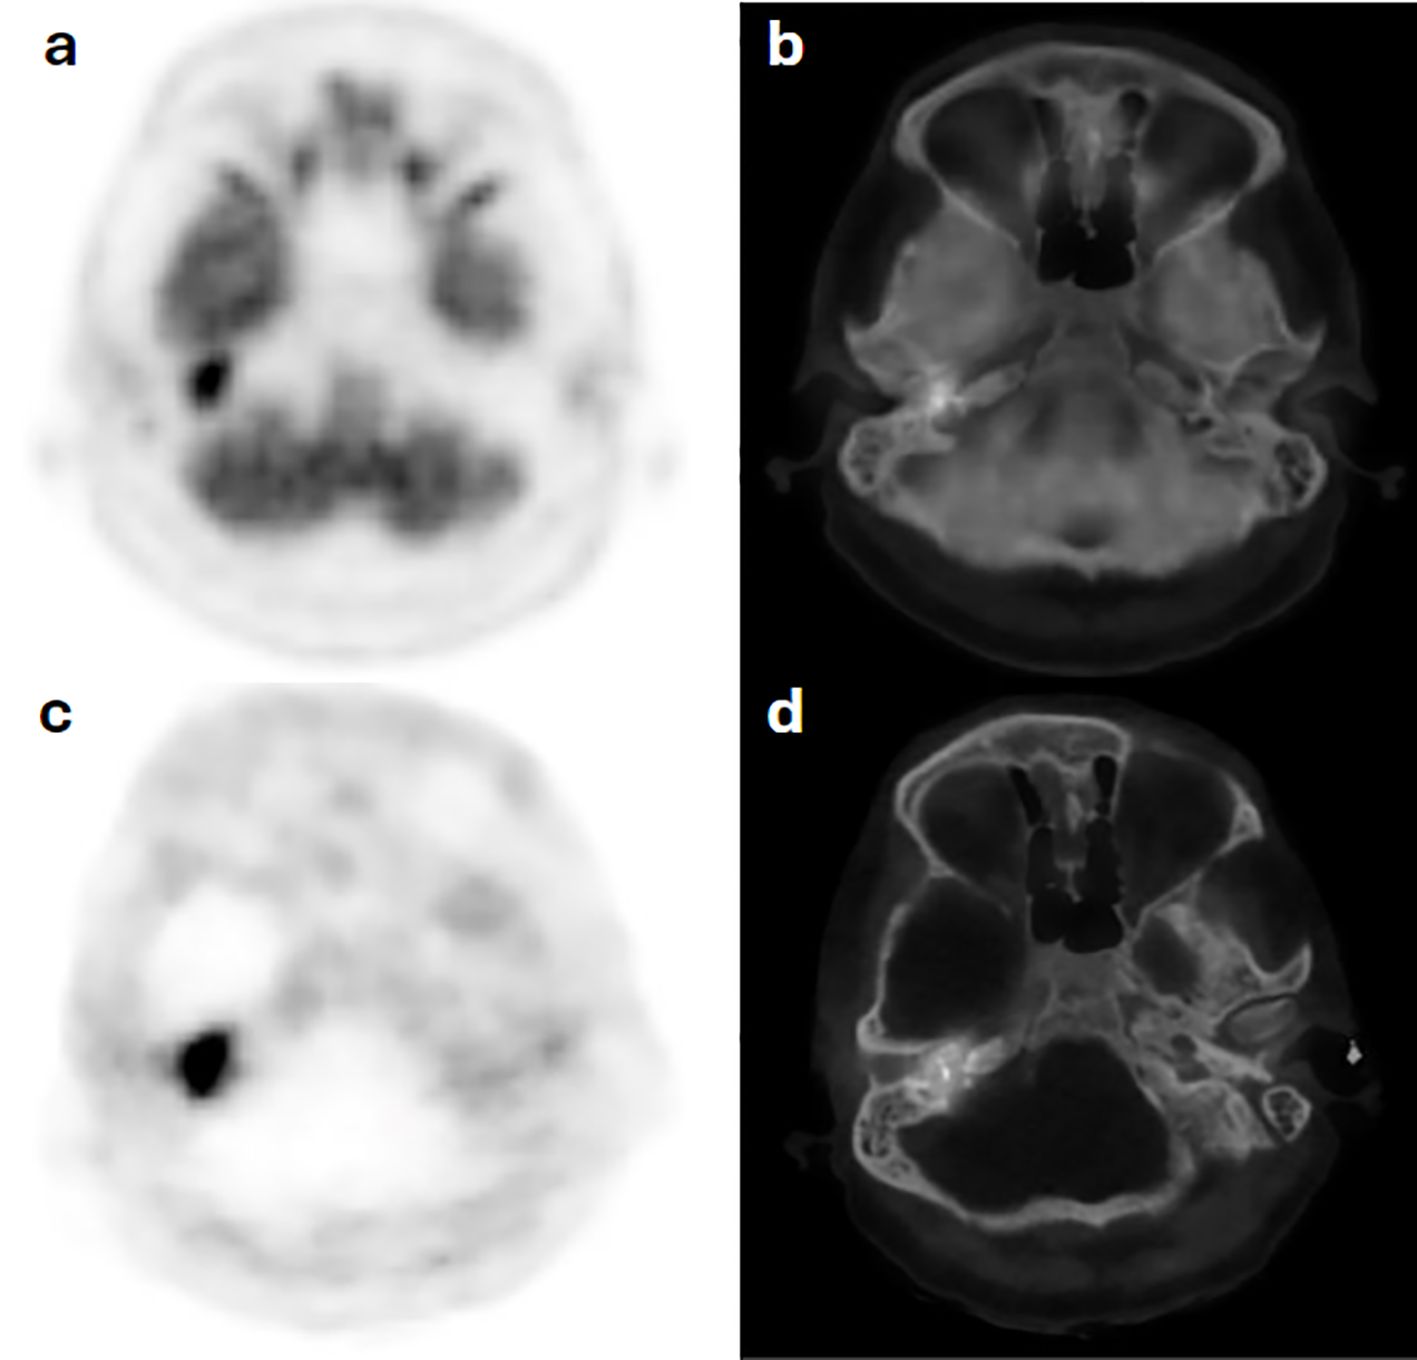

Background: Head and neck paragangliomas (HNPGs) are rare neuroendocrine tumors originating from neural crest cells, with some exhibiting malignant potential. Traditional imaging modalities, such as magnetic resonance imaging (MRI), often have limitations in detecting multifocal or metastatic disease, driving interest in more sensitive diagnostic approaches like Gallium-68 DOTATATE positron emission tomography/computed tomography (Ga-68 DOTATATE PET/CT). Methods: This retrospective study aimed to assess the effectiveness of Ga-68 DOTATATE PET/CT in the detection and management of HNPGs. Imaging data from 2015 to 2024 were reviewed, identifying four confirmed cases of HNPG. All patients underwent head and neck MRI and Ga-68 DOTATATE PET/CT scans. Data on imaging findings, treatment history, and clinical outcomes were collected and analyzed to compare the performance of Ga-68 DOTATATE PET/CT with other imaging techniques, including Iodine-123 meta-iodobenzylguanidine (I-123 MIBG) scintigraphy and Fluorine-18 fluorodeoxyglucose (F-18 FDG) PET/CT. Results: Ga-68 DOTATATE PET/CT demonstrated enhanced sensitivity in detecting both primary and metastatic lesions compared to MRI and other imaging modalities. It identified additional lesions not seen on MRI, confirmed local recurrence, and detected unsuspected metastatic sites, influencing clinical management. While Ga-68 DOTATATE PET/CT provided more diagnostic clarity than I-123 MIBG in one case, it also revealed additional metastatic sites in a patient with a succinate dehydrogenase (SDH) gene mutation, which were not detected by F-18 FDG PET/CT. Conclusion: Ga-68 DOTATATE PET/CT is a valuable imaging tool for evaluating HNPGs, with superior sensitivity in detecting both primary and metastatic lesions compared to conventional imaging. Its diagnostic advantages can significantly impact treatment planning and patient management. Integrating Ga-68 DOTATATE PET/CT into clinical guidelines for HNPG evaluation may enhance diagnostic accuracy. Further research with larger cohorts is warranted to confirm these findings and establish standardized interpretation criteria.